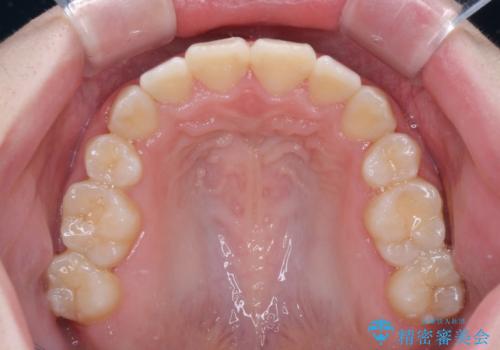

上下非接触で突出した前歯 ワイヤー装置による抜歯矯正

舌の突出癖を改善するためのトレーニングをしっかりと行っていただいたことで、比較的スムーズに治療を進めることができました。

口元の突出感もしっかりと改善することができました。